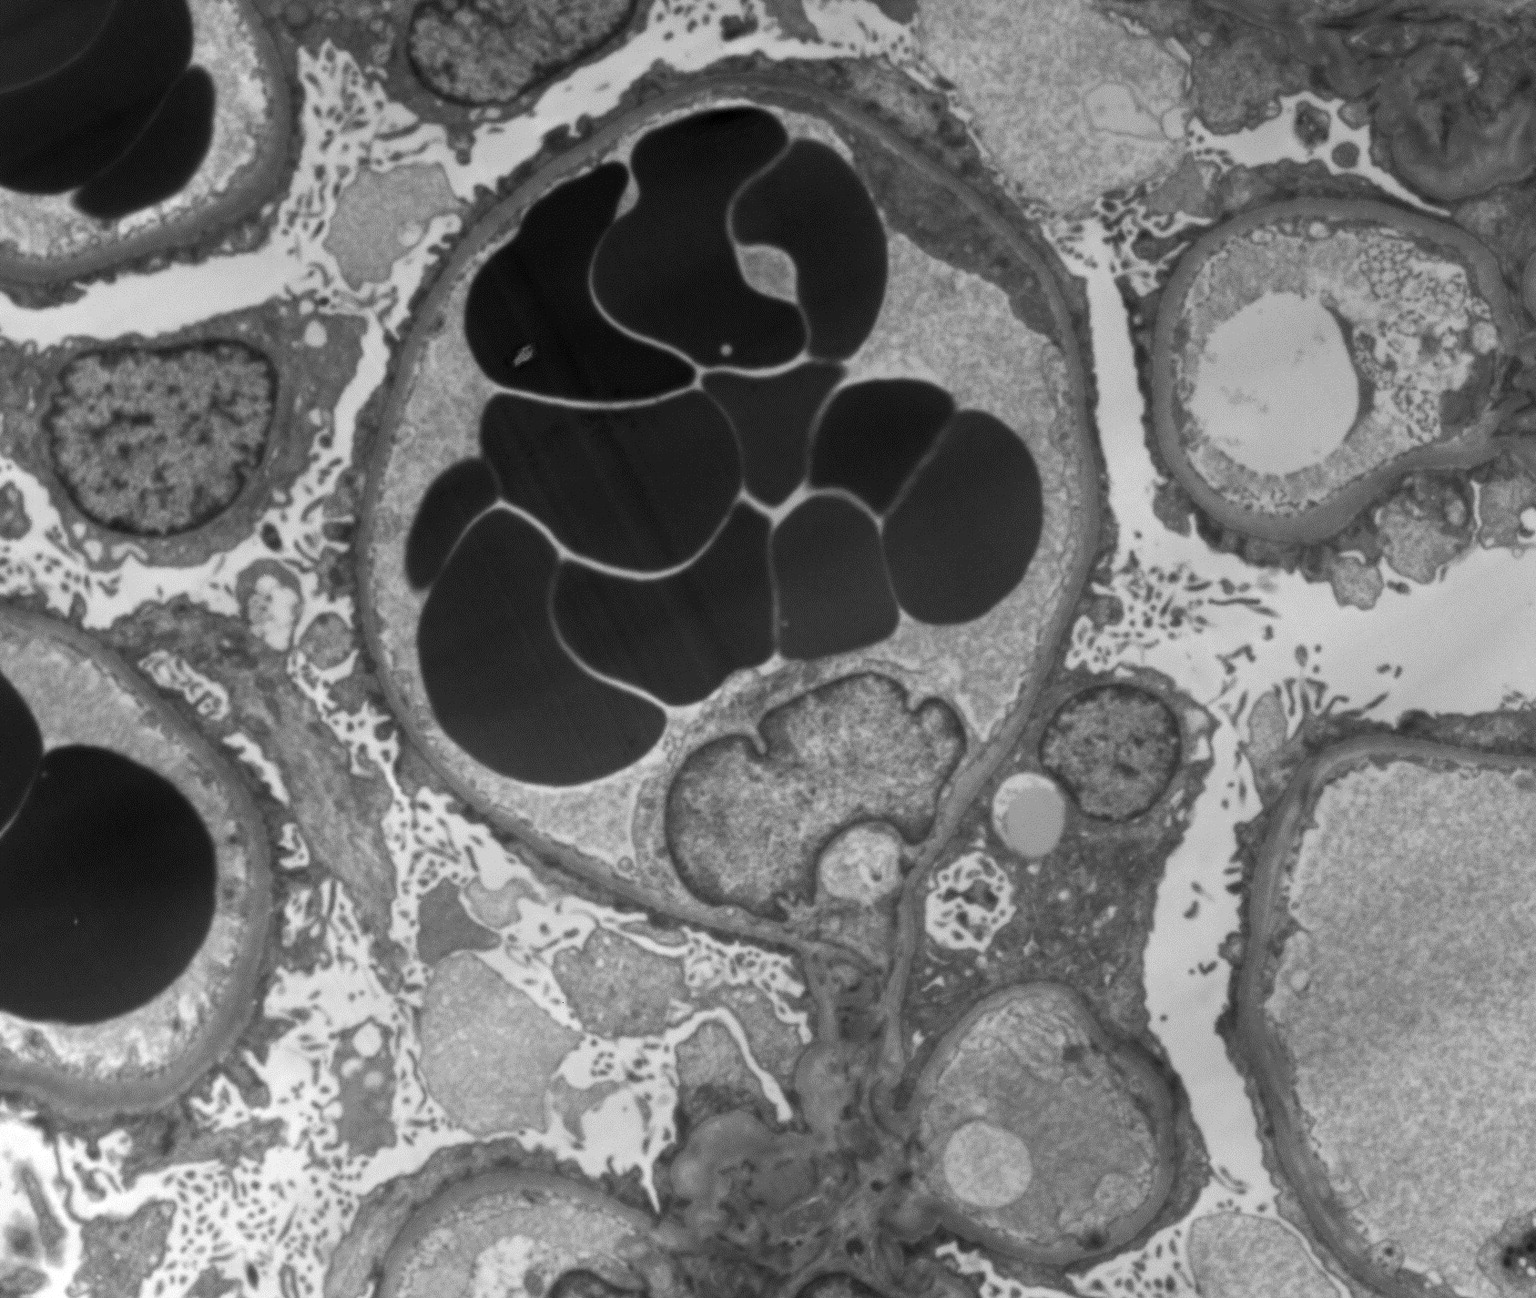

在过去几年中,我个人遇到的许多患者都与Rajora等人最近发表的AJKD in Practice文章中讨论的小插曲如出一辙。该患者患有丙型肝炎肝硬化、腹水和肝硬化[...]